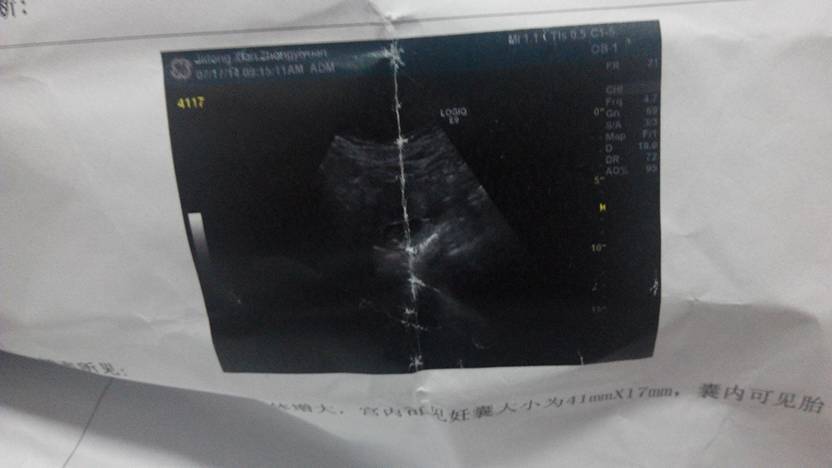

今天做的b超两个月,能看见胎心和胎牙了,请问是男宝还是女宝?第一胎,特别想要这个孩子

你这看着像长方型啊

不是说长方形的是男孩,圆型的是女孩吗?